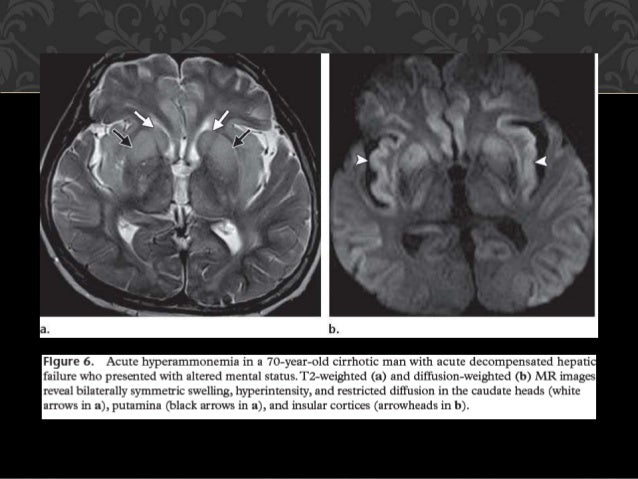

Lesiones Bilaterales De Los Ganglios De La Base Y El Talamo

es.slideshare.net